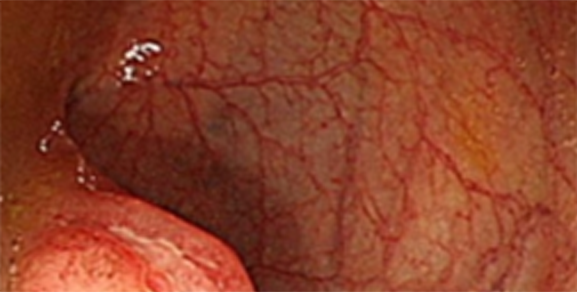

궤양성 대장염이 심화된 상태 대장내시경과 조직검사를 통해 진단합니다.

주로 내시경 소견 상 미만성, 표재성 궤양, 연속성 병변이 보이며 대부분 직장을 침범한 형태입니다.

병변부위는 직장 및 S상 결장염, 좌측결장염, 광범위 대장염으로 분류할 수 있습니다.